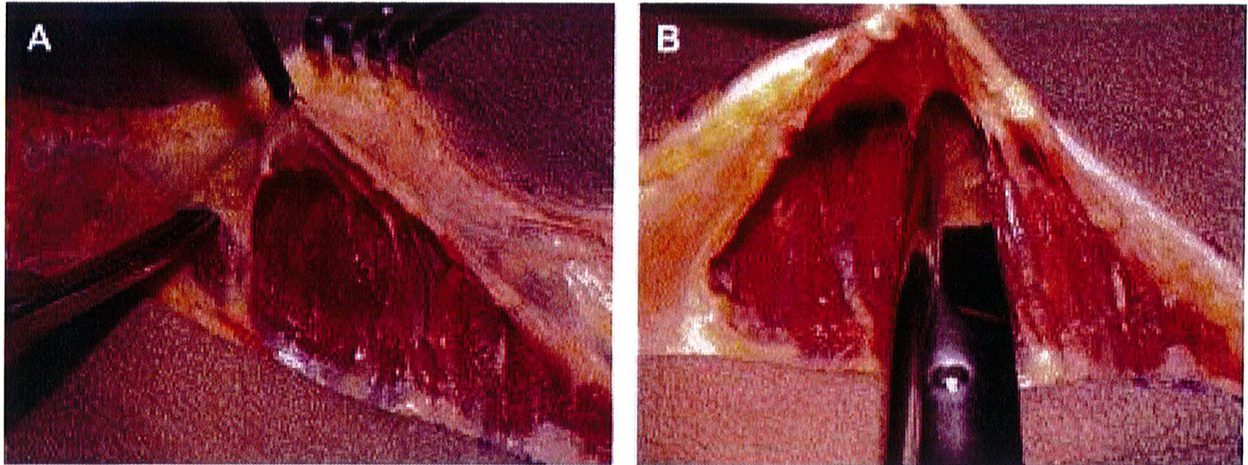

Hình. 8. (A) Phẫu thuật được lên kế hoạch, sử dụng các tiêu bản phù hợp với vùng mông của bệnh nhân với các đường rạch dài 6cm ở hai bên, trên vị trí hậu môn ít nhất 5cm. (B) Đây là hình ảnh bệnh nhân với tiền sử có bệnh lý liên quan vùng mông, đồng thời đã từng thực hiện hút mỡ mông trước đó, nên chúng tôi quyết định đặt đường rạch cao hơn bình thường để tránh các biến chứng.

Tiêm tê dưới da bằng hỗn hợp lidocain 2% với epinephrine sau đó thêm ropivacain 7.5%. Trên lỗ hậu môn 5cm, rạch hai đường mỗi đường dài 6cm về hai phía mông cho tới khi tiếp cận được lớp cân mạc ở bờ ngoài xương cùng. Từ vị trí đó, tiếp tục rạch một đường dài khoảng 8-10 cm song với bờ ngoài xương cùng, đi lên trên và cong lõm về phía mông tương ứng để bộc lộ lớp dưới cân (Hình 8).